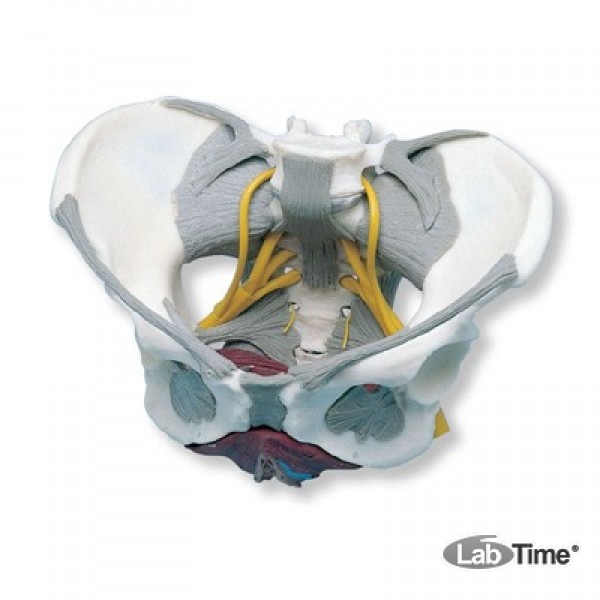

Анатомия малого таза: детальные схемы и изображения